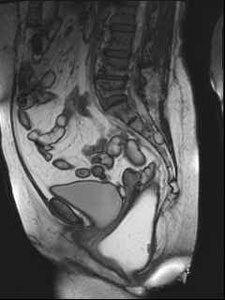

Sagittal late evacuation view shows a cystocele in the middle and posterior pelvic floor compartment. Image courtesy of Dr. Steve Halligan.

Speakers at Friday's session discussed how MRI can demonstrate the main dysfunctions of the posterior pelvic floor, and also outlined current clinical indications and implications of dynamic MRI of the pelvic floor. A major advantage of MRI is that it provides a unified view of the pelvic floor, and diseases of the anterior, middle, and posterior pelvic floor compartment can be adequately assessed in a single examination. It can also help to reduce examination time, costs, and patient discomfort, but importantly it provides a highly accurate and noninvasive evaluation of a unitary system that is often assessed and treated separately. Furthermore, because dynamic MRI offers a complete evaluation of the posterior anorectal compartment and of the anterior and middle compartments, urogynecologists and proctologists can be assisted with their clinical diagnosis, according to Maccioni.